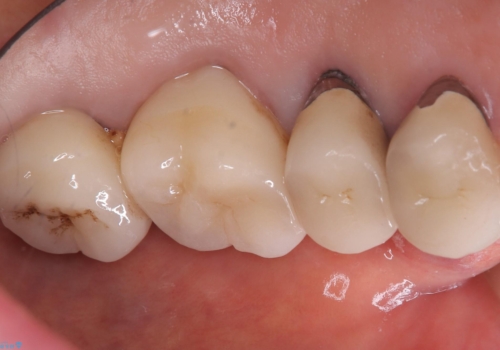

- 主訴:昔入れた被せものの境目の黒いところが気になる

クラウンの不適により境目に汚れが溜まり、黒く見えていました。

適合の良いクラウンへやり替えることとしました。

古いクラウンを除去し、不適部位から中で広がっていたカリエスを除去したのちCRにて築造、仮歯を経てセラミッククラウンをセットしています。